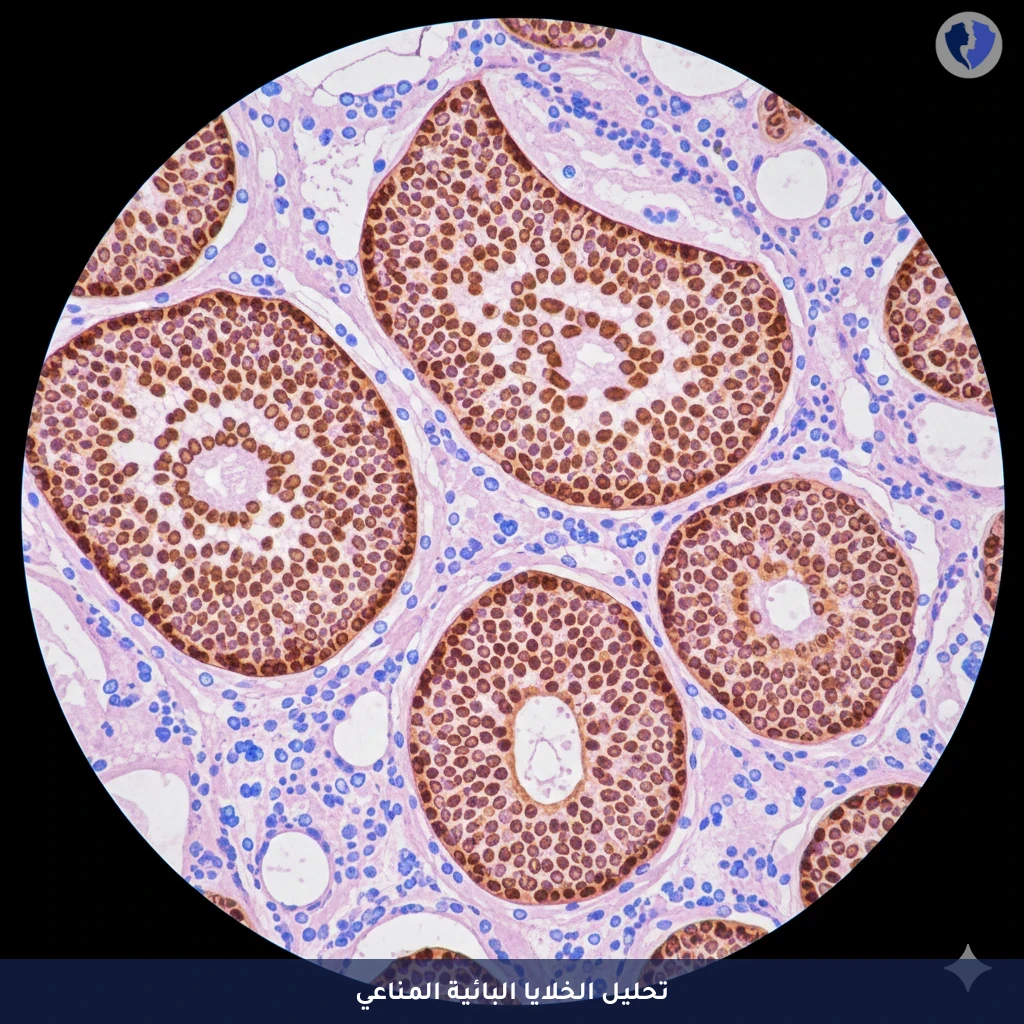

تحليل CD20 لسرطان الدم - تحليل الكيمياء النسيجية المناعية للخلايا البائية (CD20)

فحص الكيمياء الهيستولوجية المناعية (IHC) للماركر CD20 هو تقنية تستخدم أجساماً مضادة للكشف عن وجود بروتين CD20 على سطح الخلايا. يعتبر CD20 علامة نوعية للغاية لمعظم مراحل تطور الخلايا البائية (B-cells)، مما يجعله أداة تشخيصية أساسية في تصنيف الأورام اللمفاوية (B-cell lymphomas) وفي تقييم كثافة الخلايا البائية في حالات أمراض المناعة الذاتية أو الالتهابات المزمنة.